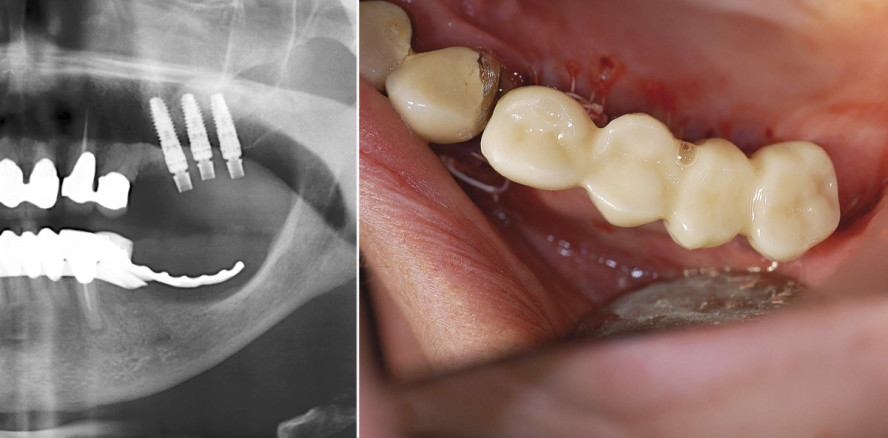

Die Insertion der Implantate erfolgte von distal nach mesial (Abb. 3), wobei die TempBase als Einbringhilfe diente. Für Regio 25 wurde eine Implantatlänge von 15 mm, für Regio 26 und 27 eine Länge von 13 mm gewählt. Nach der Insertion konnte eine für die Sofortversorgung ausreichende Primärstabilität diagnostiziert werden (Abb. 4 und 5). Es folgte das Auffüllen des restlichen Kieferhöhlenlumens und der Defektalveole Regio 24 mit dem Knochenersatzmaterial-Eigenknochengemisch. Über das Augmentat wurde eine resorbierbare Kollagenmembran gelegt, die zur besseren Haftung mit physiologischer Kochsalzlösung angefeuchtet worden war. Der trapezförmige Mukoperiostlappen konnte nun über eine minimale Periostschlitzung gelöst, nach mesial geschwenkt und so die Extraktionsalveole Regio 24 ohne Verziehen verschlossen werden. Im Bereich der Implantate wurde der Lappen durch Schlitzung zirkulär an den TempBases vernäht. Eine Röntgenkontrollaufnahme wurde angefertigt (Abb. 6).

Die Patientin wurde mit einer festsitzenden Versorgung aus der Praxis entlassen (Abb. 12a und b). Nach einer Woche konnten die Fäden entfernt werden. Der Heilungsverlauf stellte sich unauffällig dar. Nach einer neunmonatigen Einheilzeit wurde die definitive prothetische Versorgung vorgenommen (Abb. 13a und b).